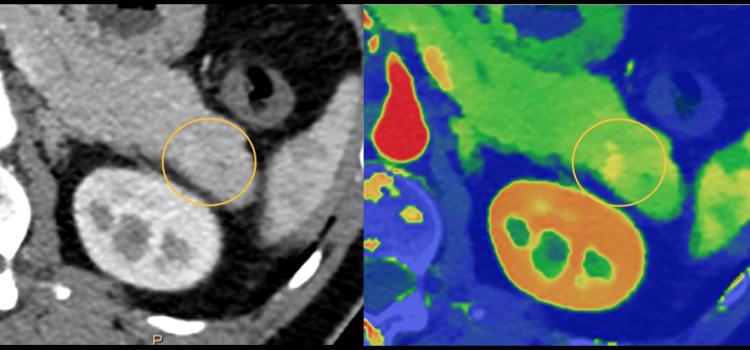

February 20, 2024 — Ultrahigh-spatial-resolution photon-counting detector CT improved assessment of coronary artery ...